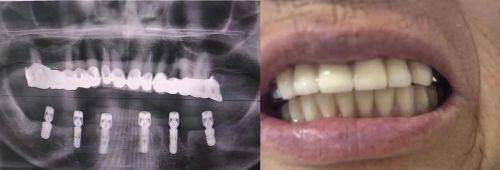

新桥口腔医院的种植牙费用明细十分清晰,患者可以根据自身情况进行选择。比如,韩国美格真种植牙的价格为4570元起,而德国ICX种植牙的价格则为9900元起。医院还提供了多种种植技术,如即刻种植、微创种植等,确保每位患者都能得到适合自己的治疗方案。值得一提的是,医院的种植牙技术在业内享有很高的声誉,医生团队实力雄厚,能够处理各种复杂病例。

在2025年,四川成都的新桥口腔医院提供多样化的种植牙服务项目,满足不同患者的需求。医院的服务项目包括单颗种植、半口种植以及全口种植,患者可以根据自己的经济情况和牙齿条件选择合适的方案。比如,ALL-ON-4全口固定种植牙的价格为120000元起,而ALL-ON-6全口固定种植牙的价格则为140000元起。医院还提供个性化的种植方案,确保每位患者都能享受到高质量的服务。

新桥口腔医院的种植牙性价比在同类医院中表现突出。以韩国登腾种植体为例,其价格为3480元起,相较于其他品牌,性价比极高。而瑞士ITI种植体虽然价格较高,但其优质的材料和技术保障了种植牙的长期效果,值得投资。医院的医生团队拥有丰富的临床经验,能够为患者提供最优质的服务,确保种植牙的成功率和舒适度。